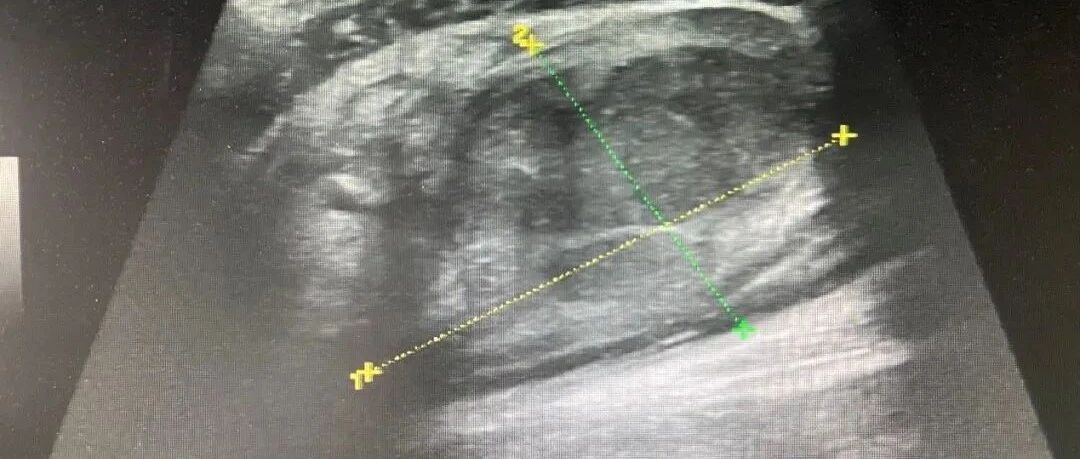

急诊床旁彩超诊断腹主动脉瘤破裂 2 例 丁香园超声时间 · 公众号 · 医学 · 1 年前 · |